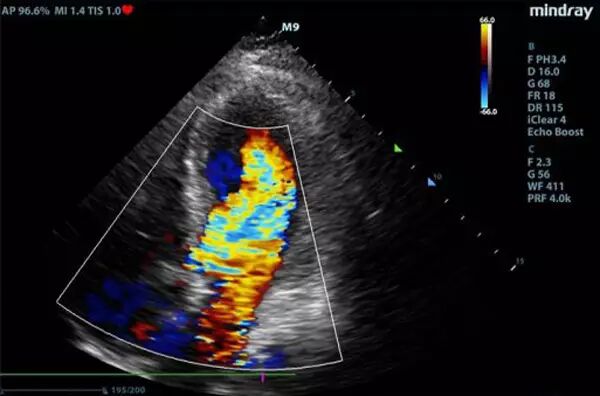

经过抢救团队对症治疗,龚先生的血压慢慢回升,尿量也多起来,乳酸指标有所下降。“在心脏状况这么差的情况下,那怕多一点液体,都有可能成为压死骆驼的最后一根稻草,患者的心脏会承受不了。”值班医生王俊峰运用重症超声这一新型武器,在心脏超声监测下给予精确输液,同时采取其它抗休克措施。经过10个小时的治疗,龚先生乳酸水平终于恢复正常,而且在十多个小时内没有再出现室颤,病情恢复出现良好兆头。

重症超声技术

传统方式下,危重病人是否发生气胸、胸水、肺水肿等,需将病人搬运至放射科做CT等影像学检查,即使床旁X线检查,也要经历拍片、洗片、读片、签发报告等环节。而重症超声因其直观、快捷、准确等特点,可直观报告病情和病因,减少了数据分析的时间,增加了临床判断的准确性,拉近了医生与病因及病情判断的距离,因而被形象地比喻为“看得见的听诊器”。

同时,由于危重病患者多半存在血流动力学不稳定,且可能进行持续机械通气或血液净化治疗,不适宜搬动,这给危重病患者的进一步明确诊断和治疗带来诸多不便。床边超声检查作为一种无创、可重复的检查技术,尤其对于心脏功能、 液体反应性等血流动力学评估作用越来越重要,为重症病人的治疗调整提供及时、准确的指导。